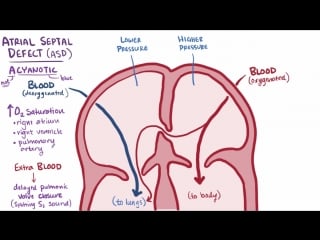

Atrial septal defect (asd)

This device helps patients with atrial septal defect (asd) also know as a hole in your heart